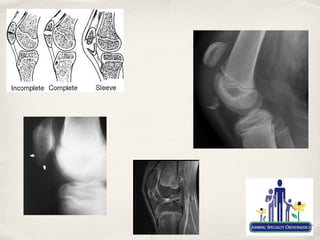

✤   Tibial Tubercle and Patella Sleeve Fractures

✤   Mostly sports related

✤   Typically occur between 12-17 y/o

✤   Usually secondary to violent contraction of quad

✤   eg. Landing a jump

✤   At tubercle, fracture occurs at junction of ossified and cartilage growth plate

✤   Sleeve fractures occur because of cartilagenous attachment at inferior pole of

the patella

✤   Difficult to diagnose, but can result in complete disruption of extensor

mechanism.